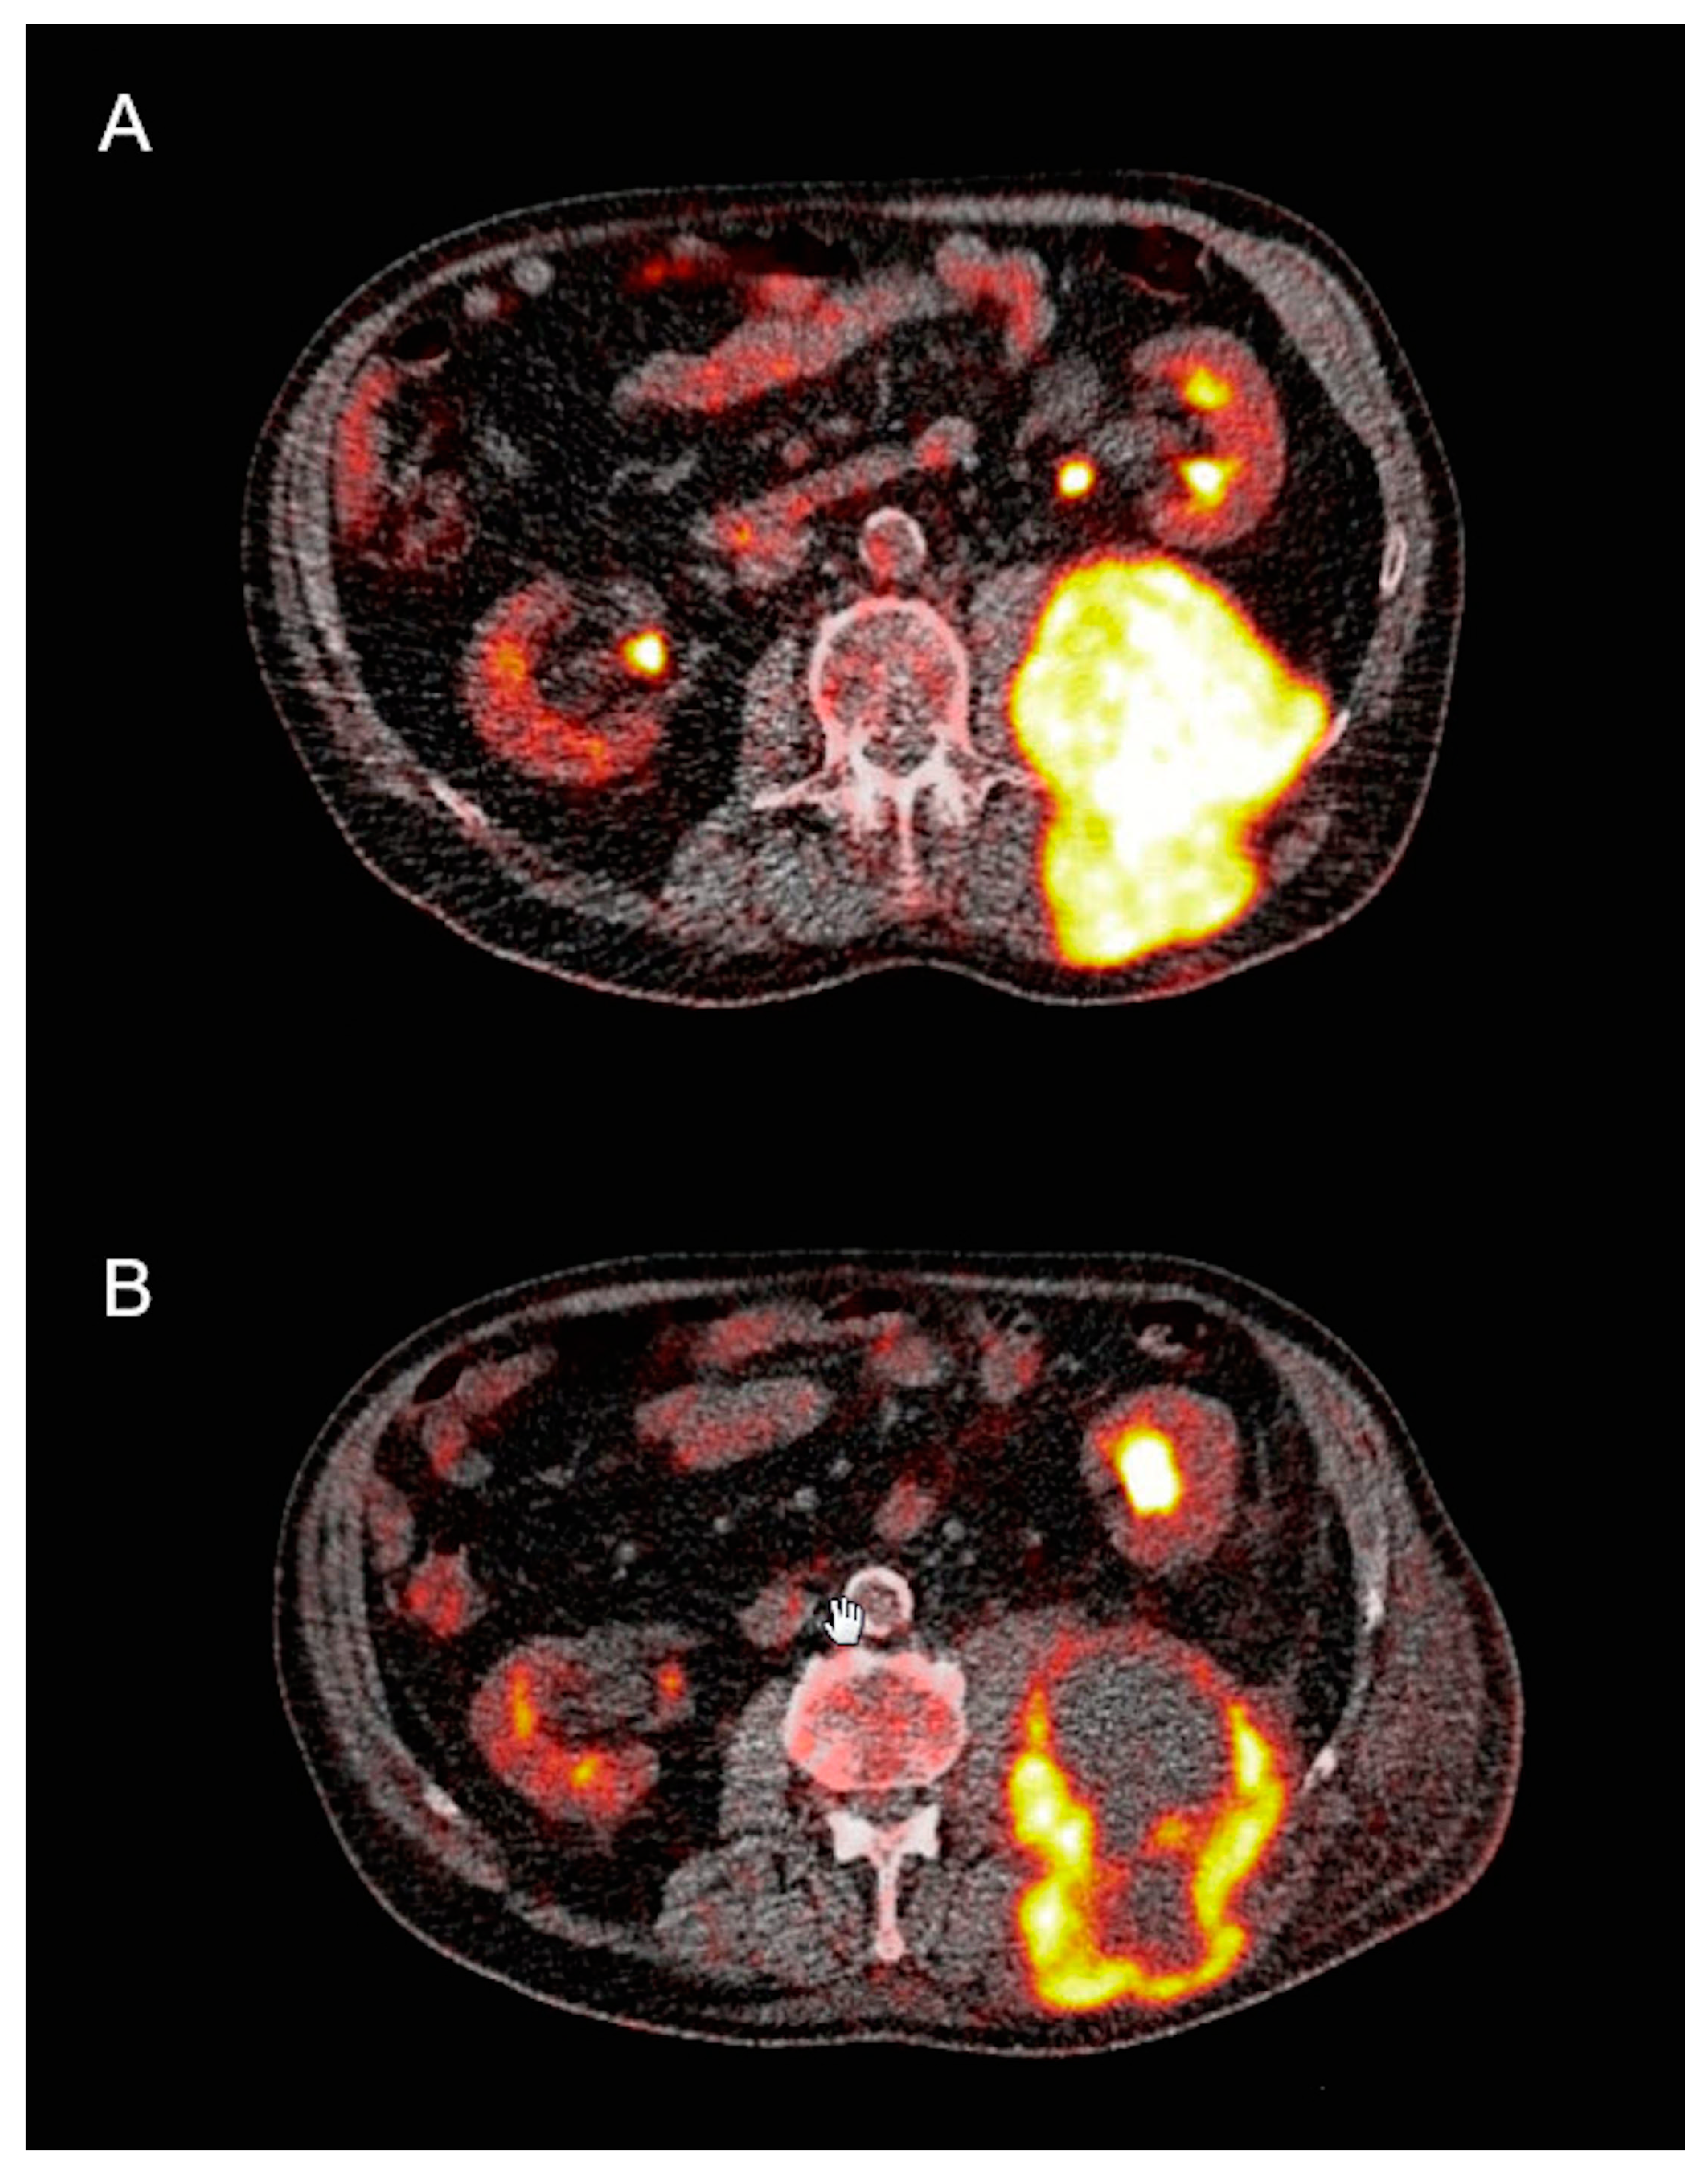

3.3. PET/CT Analysis